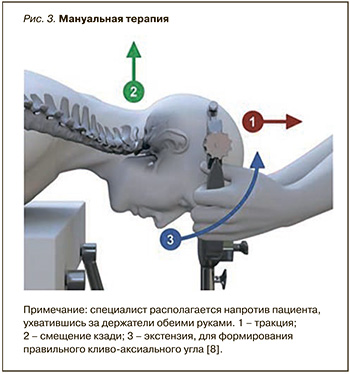

Неинвазивным методом лечения на сегодняшний день является мануальная терапия, облегчающая состояние больных. Умелые действия мануального терапевта, изображенные на рисунке 3, обеспечивают увеличение кливо-аксиального угла, сопровождаются уменьшением внутриполостного медуллярного давления с последующим улучшением ликвородинамики и купированием болевого синдрома [8].